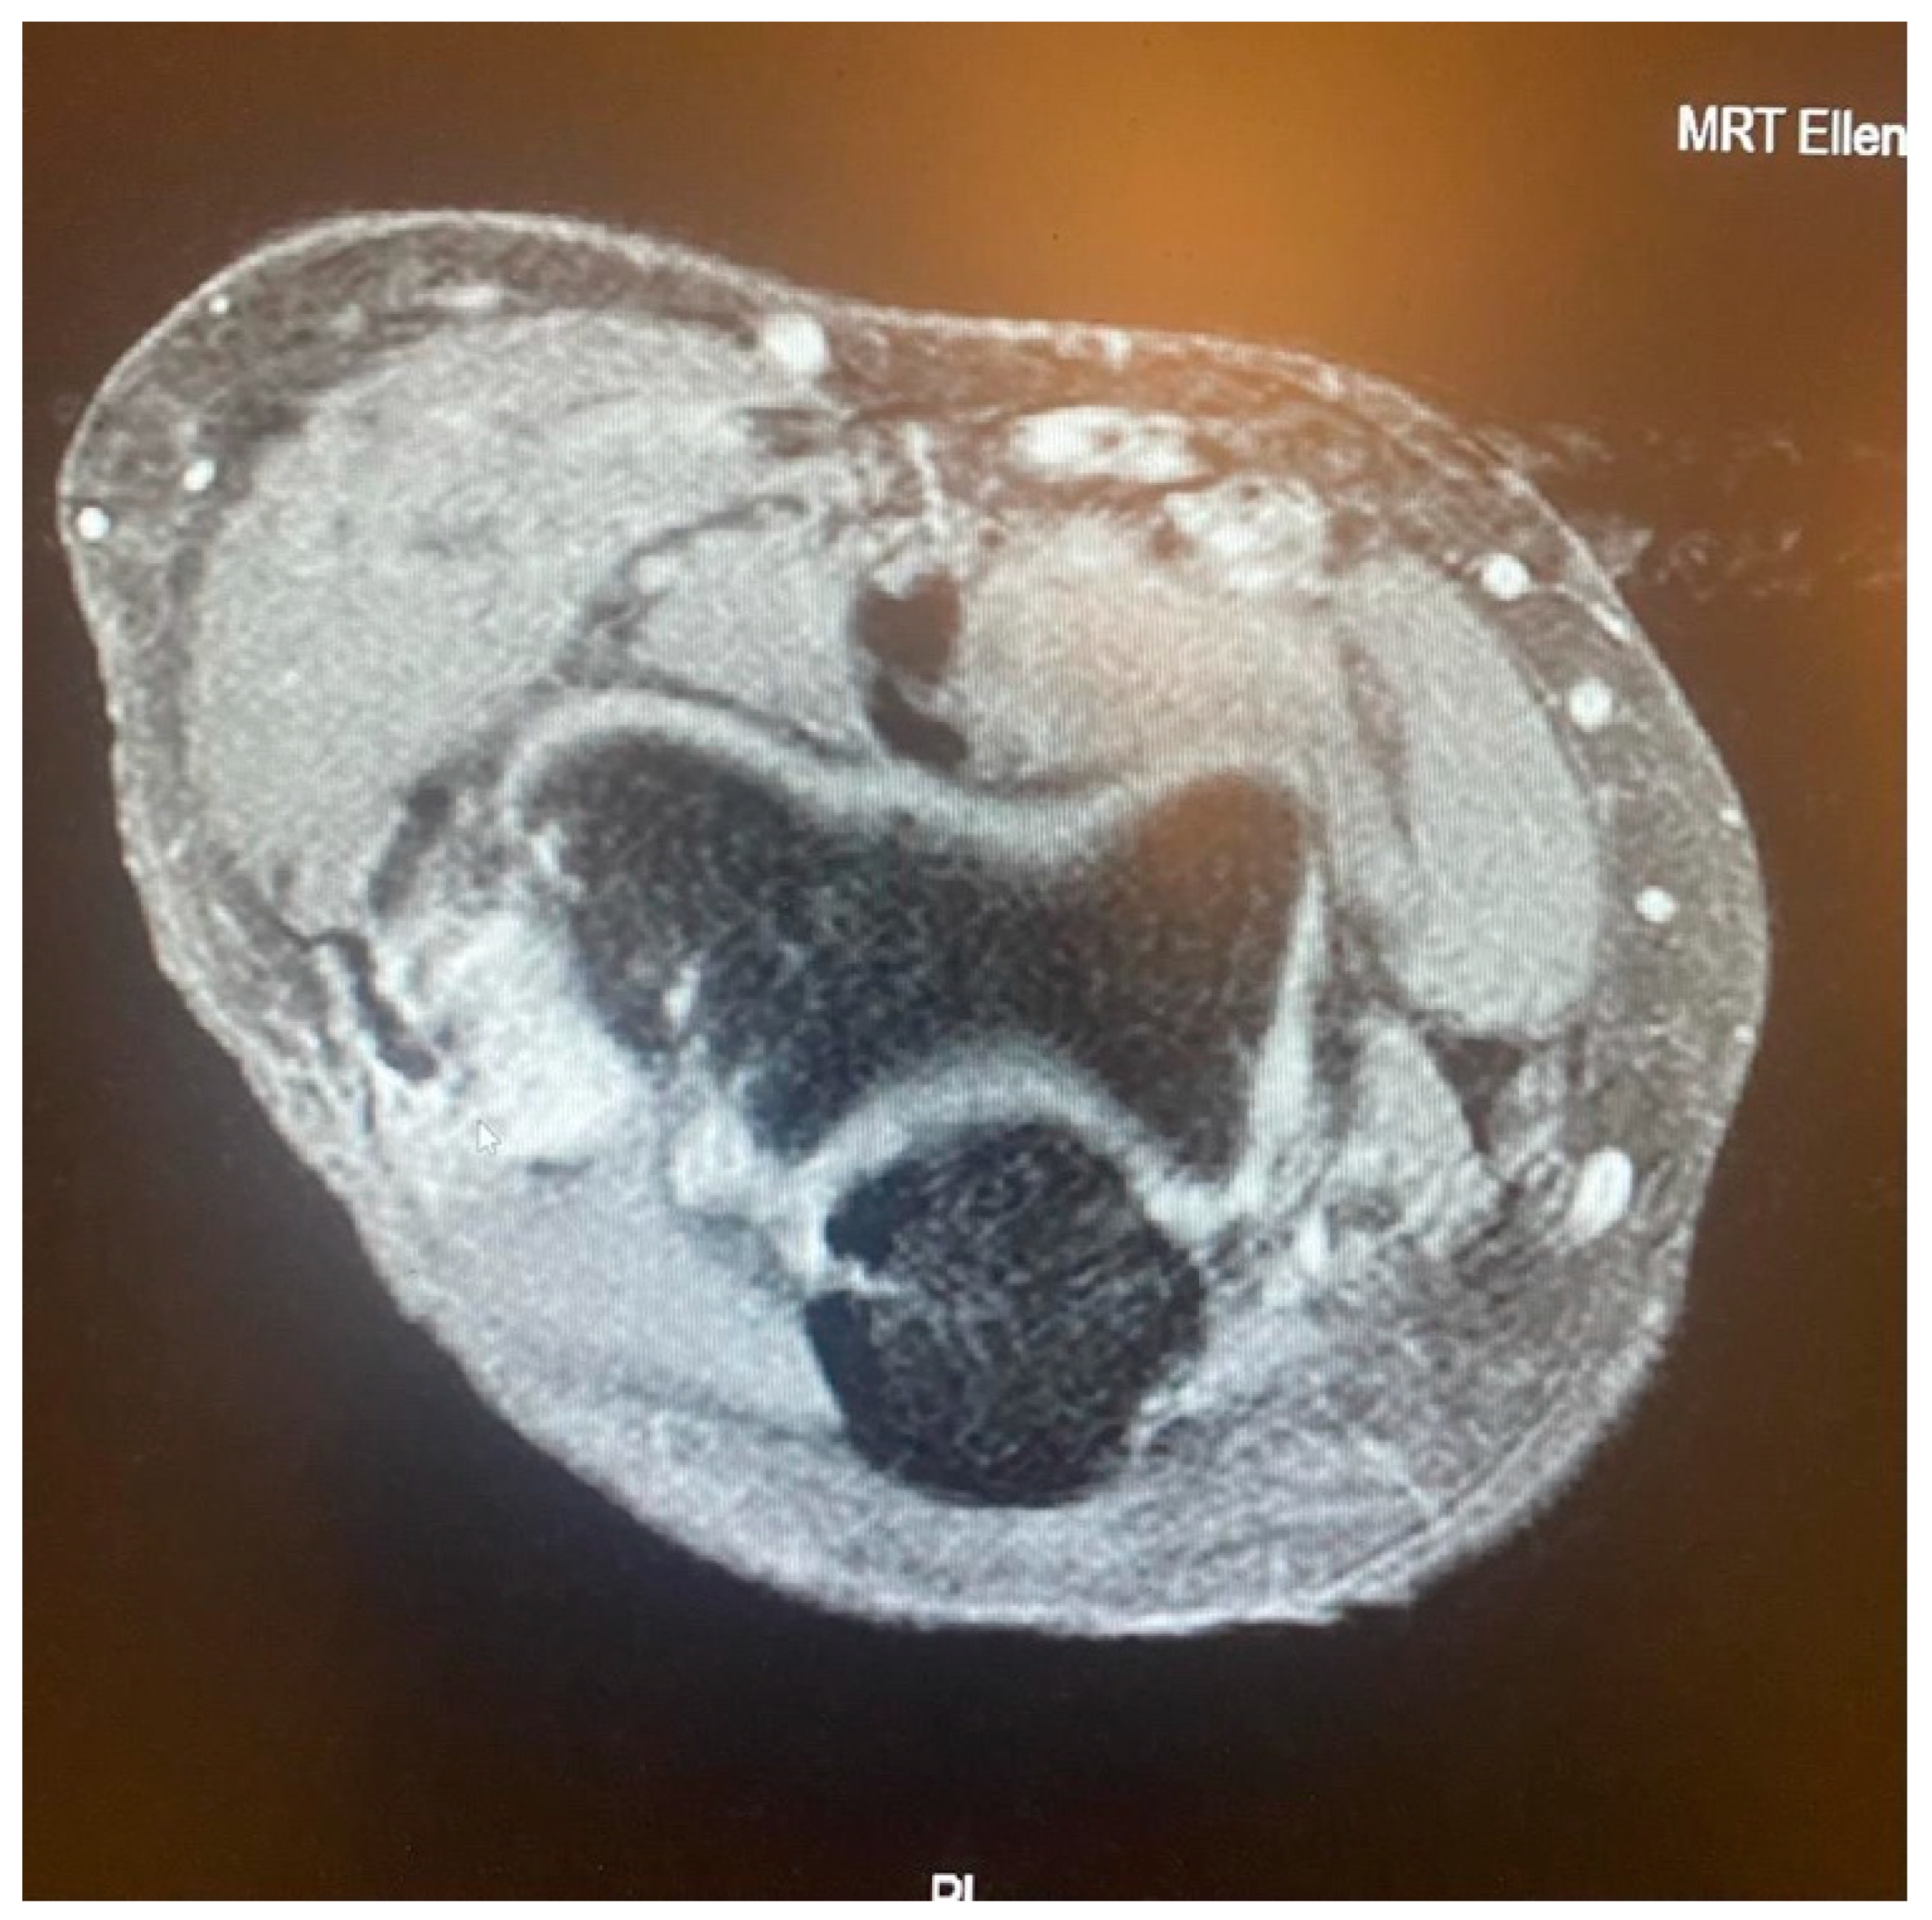

- It is contingent on the integrity of the CEO, whether it is intact, has a moderate or extensive partial tear, or is completely ruptured with or without retraction. This evaluation can be conveniently conducted via MRI.